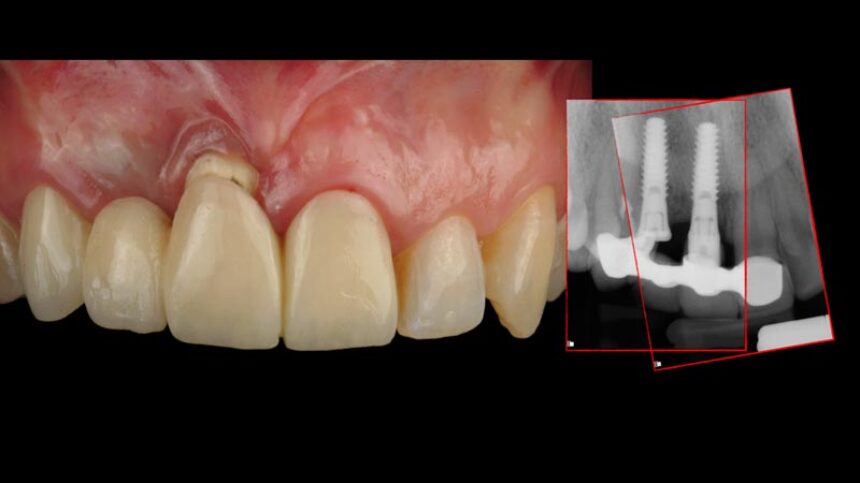

The congress will also feature Dr. Iñaki Gamborena whose lectures will focus on the key factors affecting the success of treatment in the aesthetic zone, both in patients with a purely dental arch and in implant restorations. His presentations will include the surgical and the prosthetic management of these cases, and he will also elaborate on the management of complex cases with past failures.

Decision making process for the right treatment selection option

Managing failures with implants in the esthetic area, the options.